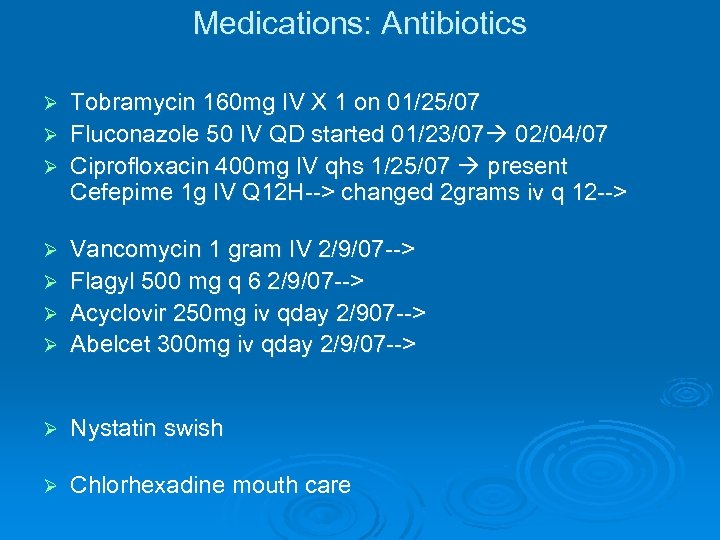

Medications: Antibiotics Tobramycin 160 mg IV X 1 on 01/25/07 Ø Fluconazole 50 IV QD started 01/23/07 02/04/07 Ø Ciprofloxacin 400 mg IV qhs 1/25/07 present Cefepime 1 g IV Q 12 H--> changed 2 grams iv q 12 --> Ø Vancomycin 1 gram IV 2/9/07 --> Ø Flagyl 500 mg q 6 2/9/07 --> Ø Acyclovir 250 mg iv qday 2/907 --> Ø Abelcet 300 mg iv qday 2/9/07 --> Ø Ø Nystatin swish Ø Chlorhexadine mouth care